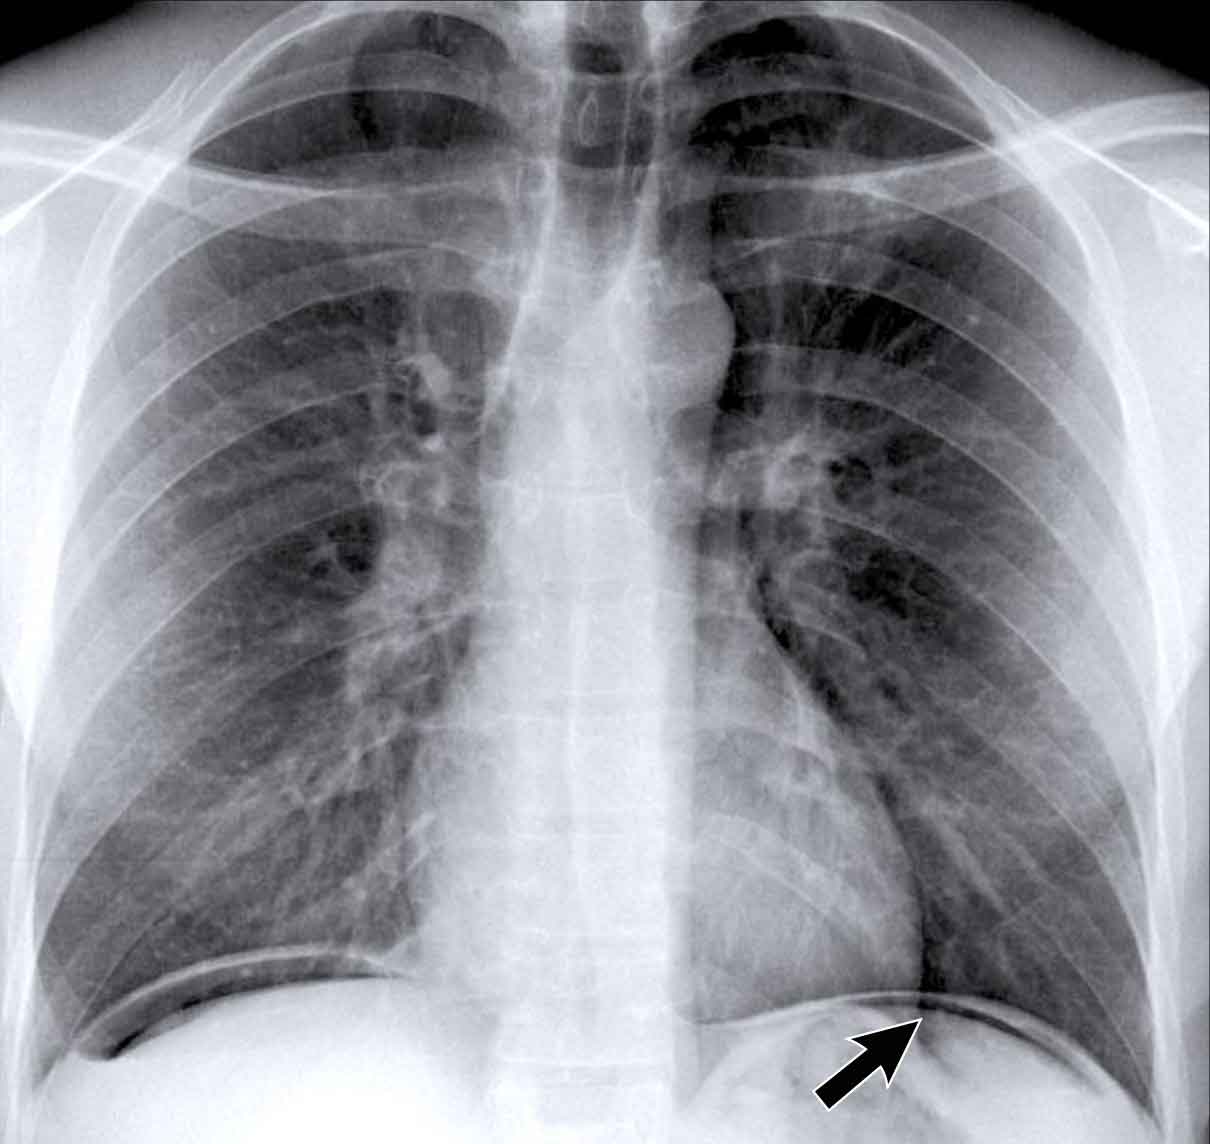

Case Example 3: Valve Replacement & Heart Failure

Post-valve replacement, a patient presents with a markedly enlarged cardiac silhouette on chest X-ray.

Findings

• A large cardiac silhouette

• There is evidence of pulmonary vascular redistribution, suggesting congestive heart failure.

Case Example 3: CT imaging

CT demonstrates a large pericardial effusion.

Tip

Always compare postoperative chest films with preoperative imaging to detect interval changes such as effusions or evolving heart failure.